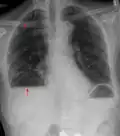

In der Medizin wird der Begriff Flüssigkeitsspiegel meist in der Radiologie verwendet, wo er die Grenzfläche zwischen Flüssigkeit einerseits und Luft oder Gas (z. B. Darmgas) andererseits in einem Hohlraum (z. B. Darm) bezeichnet. Bei entsprechender Röntgenprojektion zeigt sich eine gerade, horizontale Grenze mit höherer Transparenz oberhalb und niedrigerer Strahlendurchlässigkeit unterhalb dieses Spiegels. Beispiele für Krankheiten, bei denen das Phänomen diagnostisch genutzt wird sind:

Akute Sinusitis -

Sero- oder Hämatopneumothorax